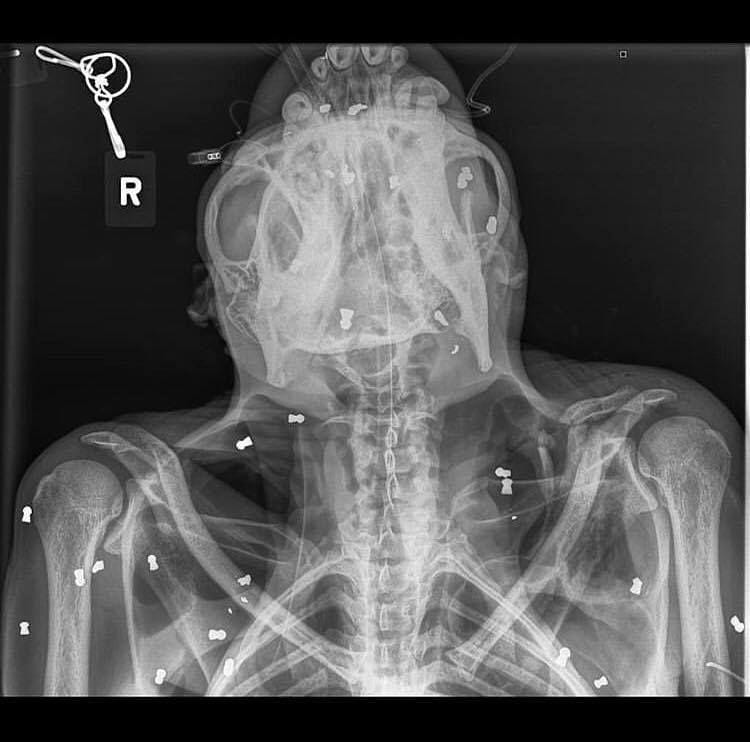

2. Usai dirontgen, ditemukan 74 butir peluru senapan angin bersarang di tubuh Orang Utan Hope

Kondisi orang utan Hope yang semakin kritis akhirnya membuat petugas BKSDA Aceh melarikannya ke sebuah klinik di Kabupaten Sibolangit, Sumatera Utara. Beruntung, orang utan berusia 35 tahun itu masih bisa diselamatkan.

Sejauh ini sudah ada tujuh butir peluru dari senapan angin yang berhasil diangkat dari tubuhnya. Selain itu, dokter juga telah melakukan operasi akibat tulang selangkanya yang patah.

Namun, yang mengejutkan ketika dokter melakukan rontgen, jumlah peluru di dalam tubuh Hope sangat banyak. Jumlahnya mencapai 74 buah. Sapto menduga Hope ditembaki menggunakan senapan angin bukan oleh dua remaja itu saja.

"Kami memiliki dugaan sebelumnya Hope juga sudah pernah ditembaki, karena dianggap mengganggu kebun. Karena ada luka di mata kiri dan setelah kami analisa, luka itu disebabkan peristiwa dua bulan sebelumnya," kata dia.